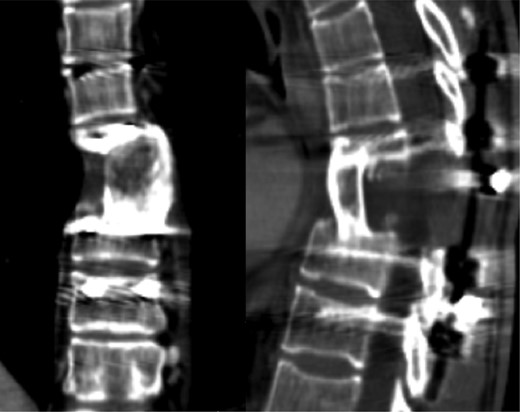

Currently, after 9 months from the initial surgery, the patient remains stable and asymptomatic with no evidence of infection or tumor relapse (Fig. 8). The follow-up imaging studies show encouraging evolution without bone graft resorption or failure of the instrumentation (Fig. 9).

CT scan with no evidence of tumor relapse or instrumentation failure.